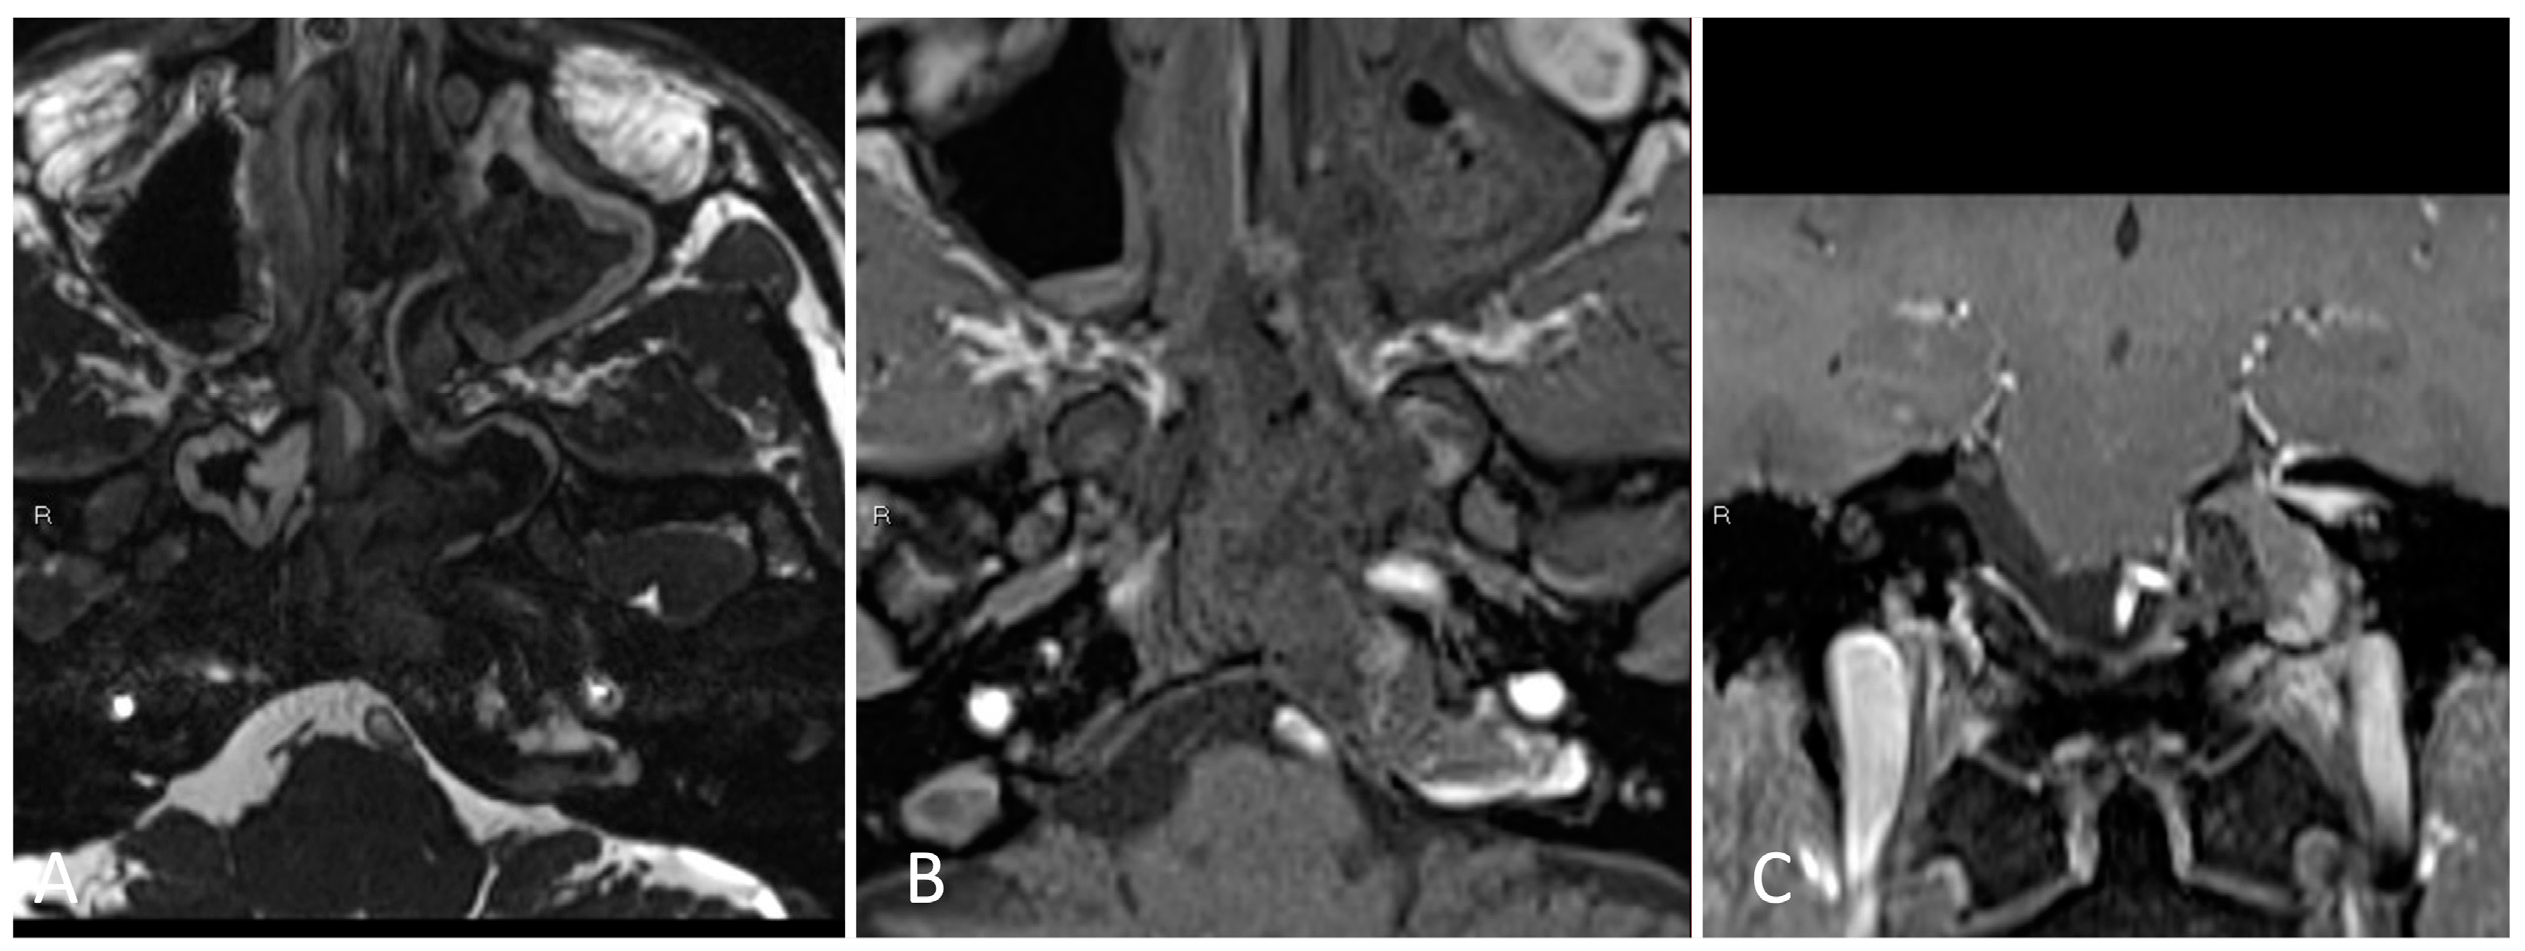

3.2.2. Illustrative Case